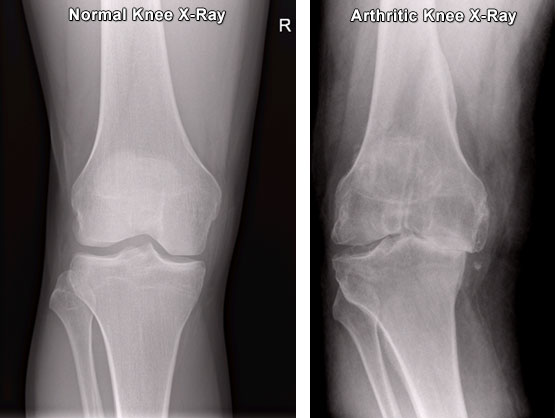

Медицинские снимки: рентген коленного сустава при остеопорозе